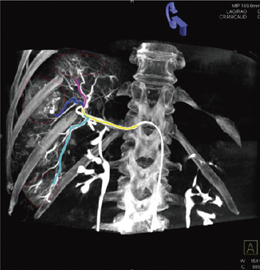

このDynaCT 360は,従来の体幹部DynaCT撮影(8秒,20秒)やLV DynaCT撮影(16秒)よりもさらに短い回転撮影時間となる6秒モードとなり,C-arm CT撮影範囲に関しても,従来のLV DynaCT撮影範囲と同等の撮影視野(Φ35cm×25cm)を確保している(図3)。この撮影技術は,LV DynaCTで行われていた220°のオフセット回転撮影を大きく上回り,全周囲となる360°の回転撮影が可能である(図4)。360°の回転撮影は,DynaCT画像の画質向上にも寄与している。従来,220°までの部分的な回転撮影から3次元画像を再構成するためには,それぞれの投影画像に対してフィルタ補正逆投影法から3次元画像再構成を行い,それ以外の撮影されていない角度範囲の画像情報に関しては,それぞれの投影角度に対して同一投影画像情報の重複を考慮し,部分的な角度範囲まで積分を拡大する必要があった。その結果,異なる投影角度からの投影データを加重し,対向データの補正を実行していた。

しかし,DynaCT 360であれば,その対向データ補正を考慮する必要がなく,360°の全周囲を実際の画像情報からフィルタ補正逆投影法を用いた3次元画像再構成を実行し,今までよりも画質完成度の高いCT Like Imagingを実現している。

図4 DynaCT 360のオフセット360°回転撮影